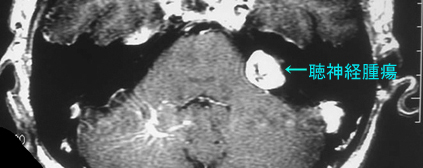

転移性脳腫瘍 聴神経腫瘍 脳動静脈奇形 頭頚部癌の一部、など

転移性脳腫瘍、原発性脳腫瘍(神経膠腫、聴神経鞘腫、髄膜腫、下垂体腫瘍、その他の腫瘍など)